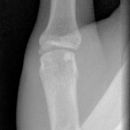

Mittelgliedbasisfraktur